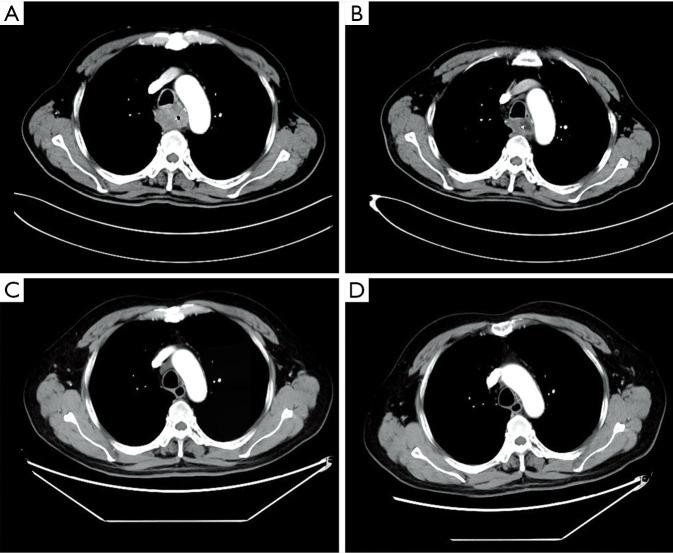

For upper thoracic esophageal cancer, surgery is difficult, and the clinical effects of chemoradiotherapy, radiotherapy, and chemotherapy are limited. Camrelizumab is a PD-1 (programmed cell death-1) antibody developed by China. There are few studies on camrelizumab in esophageal cancer. Here, a 66-year-old man was admitted to the hospital with severe dysphagia. He was diagnosed as upper thoracic esophageal squamous cell carcinoma (ESCC). The patient received nasogastric tube placement, chemotherapy with docetaxel and nedaplatin, monotherapy with camrelizumab, combination therapy with camrelizumab and docetaxel, maintenance therapy with docetaxel, successively. One year later, complete response was observed and the nasogastric tube was removed. The progression-free survival (PFS) exceeded 28 months. The patient is still being followed up. In this paper, temporary nasogastric tube feeding not only provided nutrients safely, but also won the time for immunotherapy to work. Camrelizumab-containing therapy achieved complete response with long-term survival in unresectable upper thoracic ESCC patients. Comprehensive therapy regimens involved with nasogastric tube feeding and camrelizumab-containing therapy are effective and safe in unresectable upper thoracic ESCC patients with severe dysphagia.

对于胸段上段食管癌,手术难度大,放化疗和单纯化疗的临床效果有限。卡瑞利珠单抗是中国研发的一种程序性死亡受体1(PD-1)抗体。目前关于卡瑞利珠单抗治疗食管癌的研究较少。在此,一名66岁男性因严重吞咽困难入院。他被诊断为胸段上段食管鳞状细胞癌(ESCC)。该患者先后接受了鼻胃管置入、多西他赛和顺铂化疗、卡瑞利珠单抗单药治疗、卡瑞利珠单抗与多西他赛联合治疗、多西他赛维持治疗。1年后,观察到完全缓解,鼻胃管拔除。无进展生存期(PFS)超过28个月。该患者仍在随访中。本文中,临时鼻胃管喂养不仅安全地提供了营养,还为免疫治疗发挥作用赢得了时间。含卡瑞利珠单抗的治疗方案在不可切除的胸段上段ESCC患者中实现了完全缓解并长期生存。对于有严重吞咽困难的不可切除胸段上段ESCC患者,涉及鼻胃管喂养和含卡瑞利珠单抗治疗的综合治疗方案有效且安全。